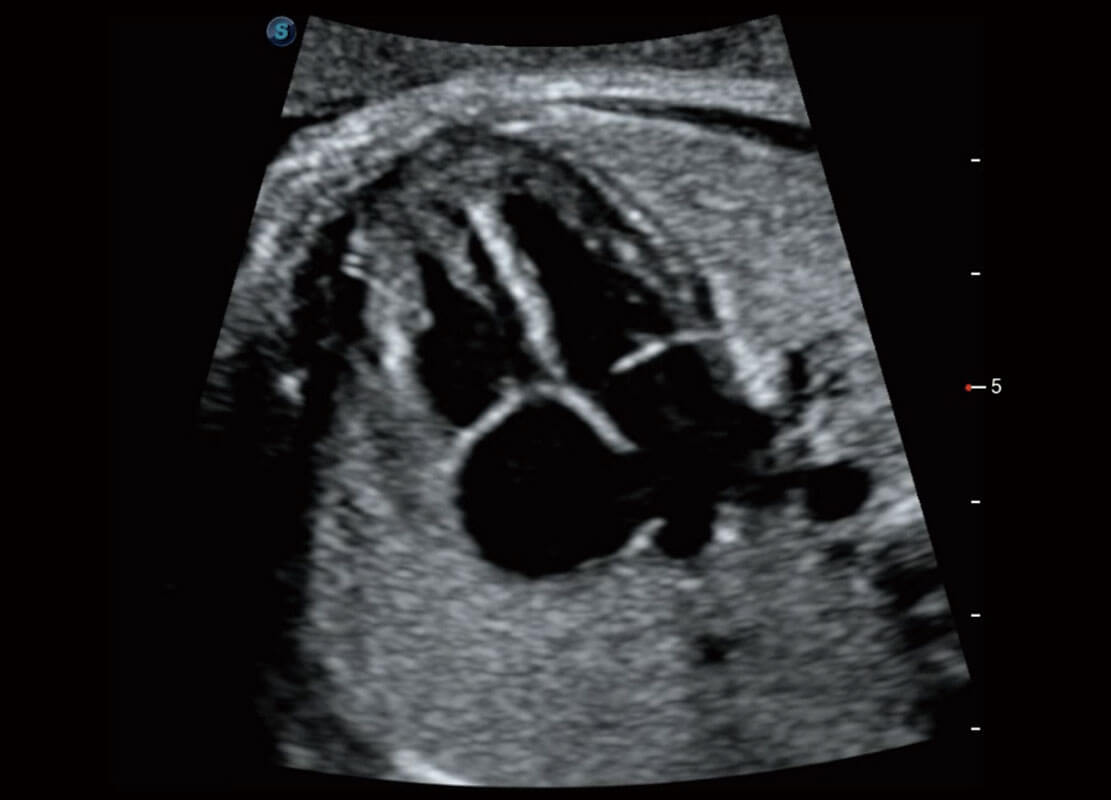

生殖健康

P60优异的图像质量搭载专科探头,在妇科基础疾病的诊断、卵泡生长的监测、输卵管通畅情况的判别等方面为您提供生殖应用方案。

• 腔内妇科-宫腔分离

• 腔内妇科-卵巢

• 腔内三维-宫内节育器

• 腔内三维-光影成像